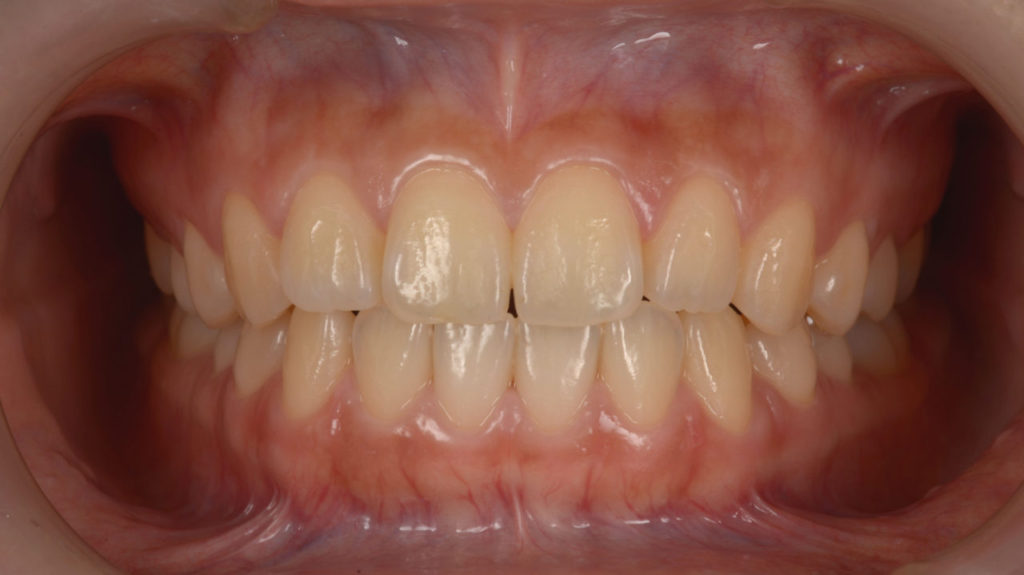

治療後

矯正を伴う咬合再構成を行った患者さんです。アンテリア ガイダンスが取れるようになりました。